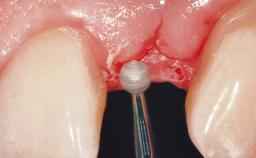

A 42-year-old female patient was referred to our clinic at the School of Dentistry of the University of São Paulo in November 2004, presenting a deficient restoration in the upper left central incisor. The clinical examination revealed no gingival retraction or any signs of gingival inflammation and, therefore, previous periodontal treatment was not considered. The patient presented a high lip line at full smile and a thin tissue biotype. This combination characterized a high-risk situation from an anatomic point of view, which required careful preoperative planning and cautious surgical execution.

Loading Protocol Immediate

Provisional Implant-Supported Prosthesis Prosthodontic margin < 3 mm apical to mucosal margin Prosthodontic margin < 3 mm apical to mucosal margin